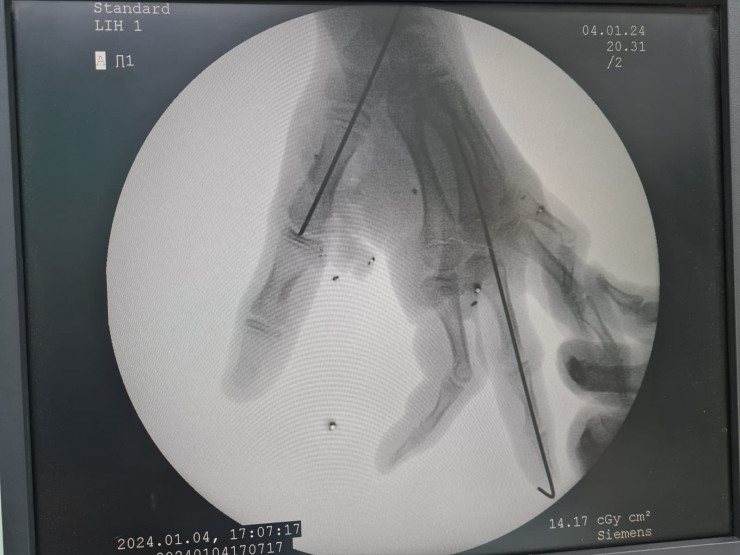

В условиях приемного отделения проведены операции: закрытая репозиция костных обломков костей с внутренней фиксацией, а также пластика местными тканями II пальца правой кисти по методу клиники. Мы буквально собирали кисти рук по лоскутам. К счастью, нам удалось спасти руки подросткам и полностью восстановить функции кисти", - рассказал травматолог Куаныш Керимше.